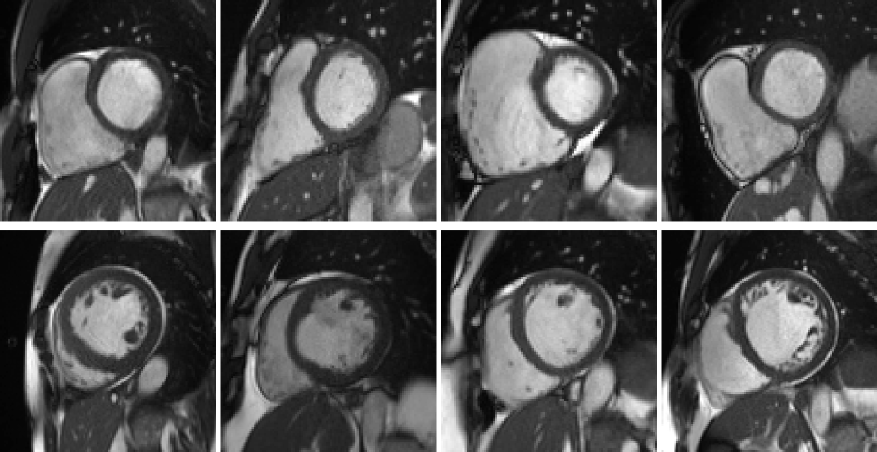

Figure 3: Examples of the cases in clusters #5 and #8. First row: example cases in cluster #5, of which the RVs appear to be exceptionally large. Second row: cases in cluster #8, of which the LVs seem to be dilated.

Among the 9 resulting clusters (termed cluster #1 to #9) of the selected model, two are of small sizes (clusters #5 and #8). We find that they actually correspond to two pathological categories according to the definition given by the ACDC challenge (RVA and DCM respectively).

Cluster #5 has 11 cases (examples are given in Figure 3). As listed in Table 2, these cases have exceptionally large right ventricles, which are above 130 𝑚𝐿/m2𝑚𝐿superscript𝑚2\mathit{mL/m^{2}}. In the ACDC challenge, the RVA cases are described as of RVC volumes higher than 110 𝑚𝐿/m2𝑚𝐿superscript𝑚2\mathit{mL/m^{2}} or RVC ejection fraction lower than 40%. Hence according to the definition of ACDC, cluster #5 is a group of cases belonging to RVA.

Cluster #8 has 4 cases (examples are given in Figure 3). As shown in Table 3, these cases have large LVC volumes at ED (above 130 𝑚𝐿/m2𝑚𝐿superscript𝑚2\mathit{mL/m^{2}}) and low LVC ejection fractions (below 30%). In the ACDC challenge, DCM cases are those with LVC volumes larger than 100 𝑚𝐿/m2𝑚𝐿superscript𝑚2\mathit{mL/m^{2}} and LVC ejection fraction lower than 40%. So cluster #8 is a group of DCM cases according to ACDC. In addition, we find that the ground-truth measures of LVC volume at ED and LVC ejection fraction are available for all 4 cases in UK Biobank (last two columns in Table 3). It is straightforward to see in Table 3 that the measures generated by our feature extraction method are quite close to the ground-truth.